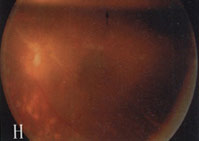

6、其他臟器併發症表現心血管病變如心力衰竭、心肌梗死。神經病變如周圍神經病變。累及自主神經時可出現神經源性膀胱。視網膜病變,糖尿病腎病嚴重時幾乎100%合併視網膜病變,但有嚴重視網膜病變者不一定有明顯的腎臟病變。當糖尿病腎病進展時,視網膜病變常加速惡化。

2.糖尿病視網膜病變和腎臟微血管病二者可同時存在。視網膜病變可繼發於糖尿病腎腎病以後,一般認為網膜病變的發生率高於腎微血管病變。因網膜病變易於觀察,而糖尿病腎腎病難於診斷,所以糖尿病人一旦出現網膜病變,要警惕腎病發生。